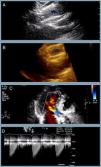

At one-year follow-up the patient remains in NHYA class II, with NT-proBNP level of 510 pg/ml. Transthoracic echocardiography revealed the two bioprostheses overlapping with appropriate transprosthetic gradients and associated mild to moderate leak (Figure 2).

The last transthoracic echocardiography (at one-year follow-up) revealing (A and B) partial overlapping of the two bioprostheses (blue asterisk) (two- and three-dimensional respectively); (C) mild to moderate associated periprosthetic leak; (D) appropriate transprosthetic gradients (maximum and mean of 20 mmHg and 10 mmHg, respectively).